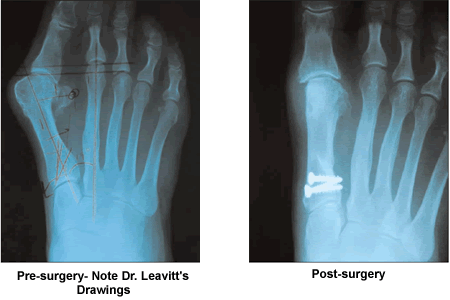

I am so glad I took her advice. Upon entering his office for the first time, his staff was extremely cordial and highly efficient. After examining the X-rays taken on site, he thoroughly explained exactly what surgical method he would use, and why, to correct the bunions. I asked him a series of questions I had prepared, and took notes as he addressed each one. Primarily, I asked about the length and expected outcome of the surgery along with pain and recuperation issues. He gave me relevant material to take home and read and urged me to call him if I had any other questions or concerns.

Dr. Leavitt's incredible surgical skills have totally eliminated a longstanding hereditary condition that was very painful and disfiguring. I would highly encourage anyone who has been apprehensive about bunion surgery to see him for a consultation.